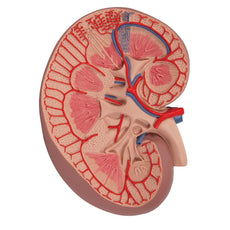

- Kidney with adrenal gland.

One front half of a kidney is removable from the anatomical model of the urinary system. With easy to change male insert (bladder and prostate, front and rear half) and female insert (bladder, womb and ovaries, 2 lateral halves) the Urinary System model is a great teaching tool.